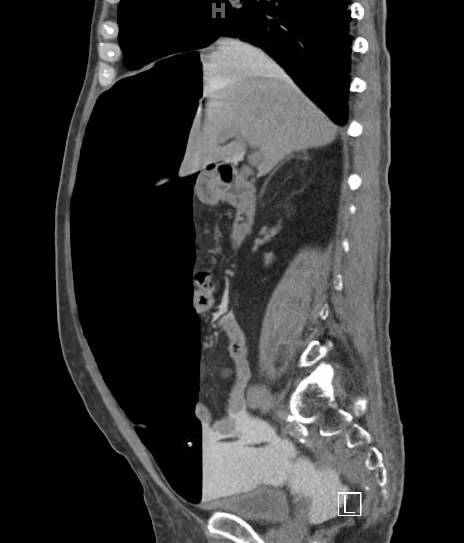

You are working one evening when an elderly gentleman is sent in by his nephrologist for abdominal pain.  The patient has a history of renal failure and is on peritoneal dialysis.  Last evening, he developed sudden, severe abdominal pain and was unable to perform PD at home.  Today, he went to the outpatient dialysis unit where they withdrew some fluid.  His nephrologist ordered a CT of the abdomen and pelvis which demonstrated the following:

Final diagnosis: Iatrogenic pneumoperitoneum from injection of air through peritoneal dialysis catheter

Case Conclusion:   The patient was noted to have a large amount of free air on his CT scan (which was actually a CT peritoneogram in which contrast was injected into the peritoneum via the PD catheter, thereby accounting for contrast in the peritoneal space).   The air was evacuated from his peritoneum via the dialysis catheter and his pain improved. An upper GI series performed with water-soluble contrast was negative for perforation.  The patient was admitted for serial abdominal exams and discharged to home the next day.  It was determined that the patient likely had inadvertently allowed air to enter his peritoneum via the PD catheter and he was re-instructed on proper technique.